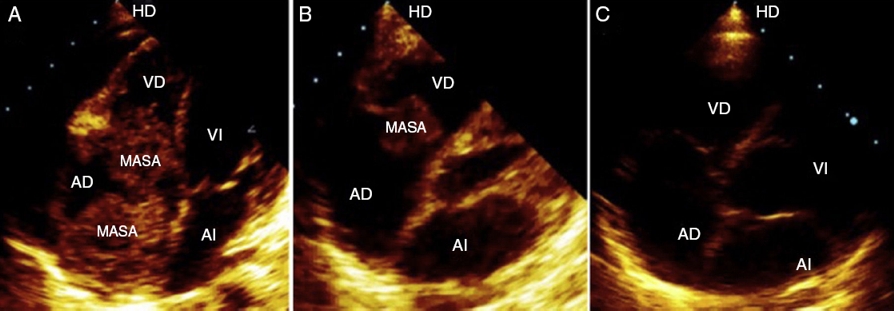

En la evaluación cardiológica, el paciente se encontraba asintomático cardiovascular, con signos vitales estables y examen físico cardiológico normal. El electrocardiograma en ritmo sinusal con frecuencia 71 lpm, trastornos de la conducción del ventrículo derecho y alteraciones difusas de la repolarización ventricular. La ecocardiografía transtorácica mostró 3 masas intracardiacas en la aurícula derecha de 3,8 × 3, 3 × 2,5 y 2 × 2 cm, respectivamente; adosadas al tabique interauricular, con protrusión durante la diástole a través de la válvula tricúspide (Fig. 1A), siendo considerado como progresión tumoral, se hizo el diagnóstico diferencial con trombo vs. endocarditis infecciosa. La función ventricular normal con fracción de expulsión del 70% y el pericardio de características normales.

Figura 1 A) Imagen ecocardiográfica, en el plano apical de 4 cámaras, que muestra 3 masas en aurícula derecha que protruyen al ventrículo derecho durante la diástole, antes del tratamiento (25/08/2015). B) Después del tratamiento con quimioterapia prefase se observa una reducción del 80% de las masas tumorales, (01/09/2015). C) Después del tratamiento con quimioterapia bloque A y bloque B, hay una remisión completa de las masas tumorales.

El 25 de agosto de 2015 ingresa en la unidad de cuidados intensivos (UCI) para inicio del tratamiento con quimioterapia prefase: hidratación, alcalinización, dexametasona, vincristina y ciclofosfamida, con manejo de cuadro de lisis tumoral; siendo dado de alta de la UCI el 30/08/2015. El ecocardiograma de control mostró una reducción de la masa cardiaca en un 80% (Fig. 1B).

En el ecocardiograma del 28/10/2015 no se observa masa cardiaca (Fig. 1C), y la función ventricular es normal. El paciente tuvo una evolución clínica favorable. Actualmente continua en quimioterapia hasta completar 3 ciclos A y 3 ciclos B.